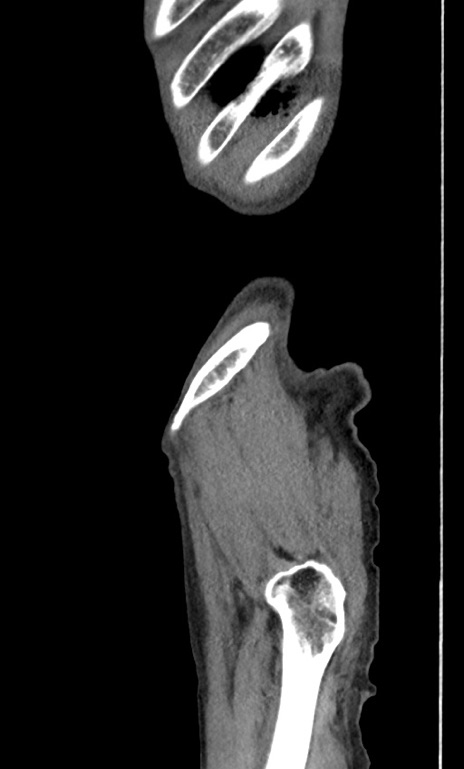

症例3(矢状断像)

【症例】 70歳代男性

【主訴】右鼠径部腫瘤、疼痛

【既往歴】膀胱癌にて膀胱全摘、両側尿管皮膚瘻